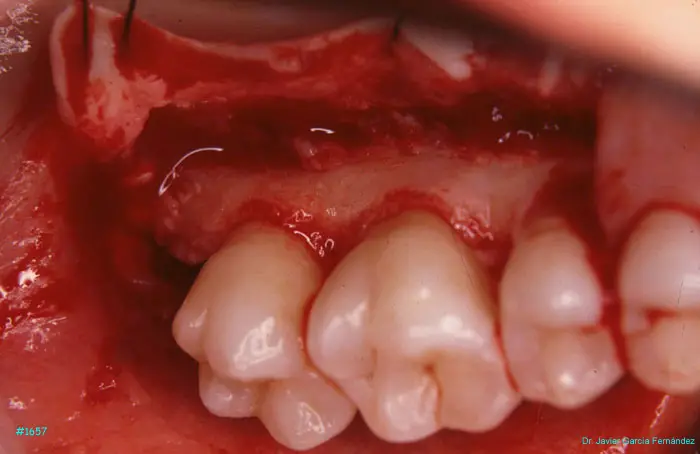

Atlas of Surgical Techniques in Periodontics. Chapter IV. Atlas de Técnicas Quirúrgica en Periodoncia

image 170